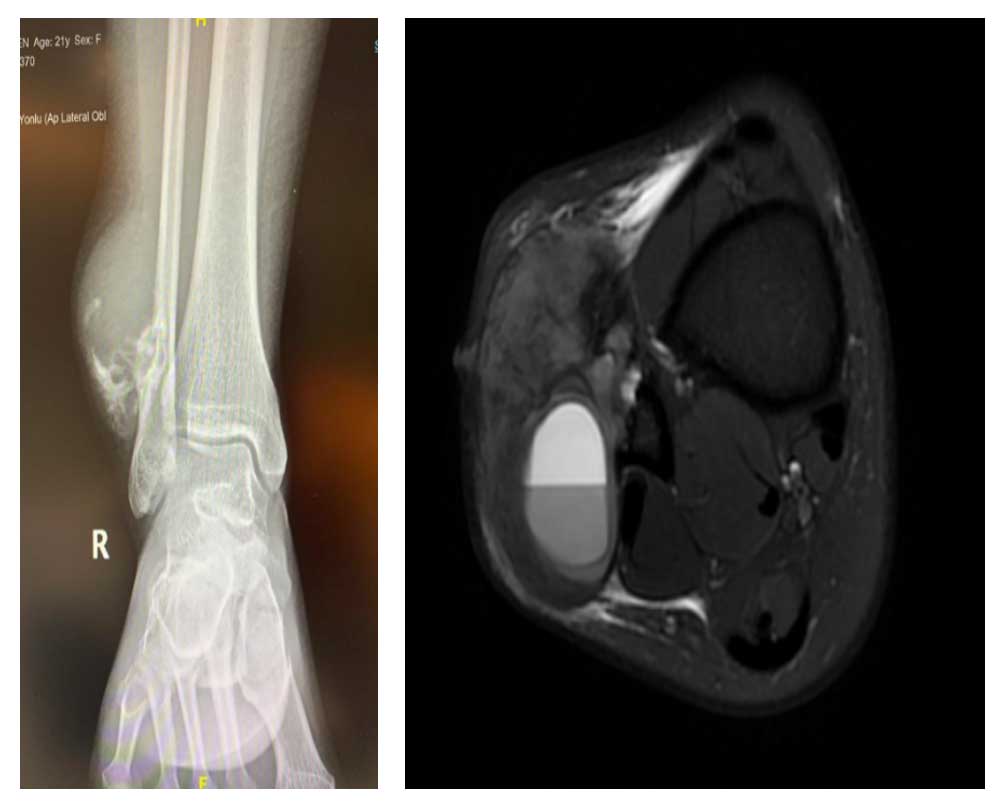

Ameliyat Öncesi: Röntgende distal fibulada harabiyet ve düzensizlik, MR’da yumuşak doku kitlesi ve çevreleyen ödem görülmekte.